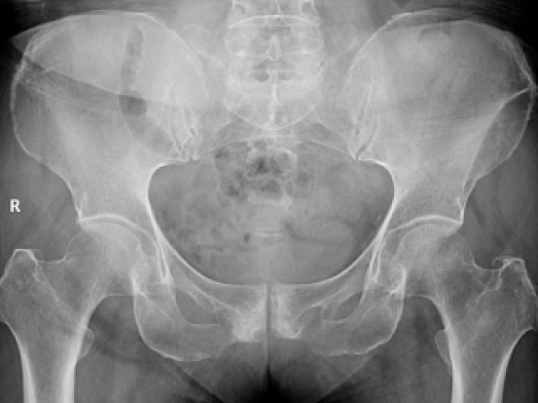

宝妈罗女士产后,出现“门户处”(耻骨联合区)疼痛不适,压痛明显,妇科超声检查未发现异常,考虑为产后并发症耻骨联合分离。

宝妈未引起重视,一个多月后,疼痛仍不能缓解且有加重趋势,遂来我院影像科拍骨盆DR片。

发现其耻骨联合间隙稍增宽,双侧关节面可见硬化、毛糙、囊性改变,考虑为耻骨联合骨软骨炎。采取对症治疗,疗效显著,症状得到明显改善。

主要影像表现有耻骨联合间隙正常或增宽,骨缘骨质硬化,部分囊变,多见于双侧,也可单侧;耻骨联合骨缘锯齿状、鼠咬状、虫蚀状骨质破坏,边缘不光整,有时可见游离小骨块,有时耻骨联合呈不同程度错位。